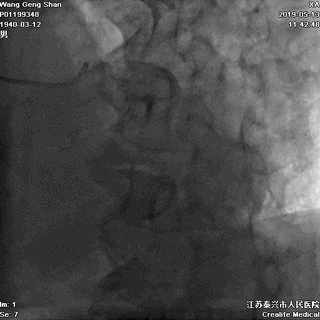

06 LM-LAD支架后扩张

交换回旋支导丝,非顺应性球囊顺序高压扩张

07 LM支架近段优化(POT)

左主干近段用大一号非顺应性球囊行高压扩张

IVUS评估,支架贴壁良好。